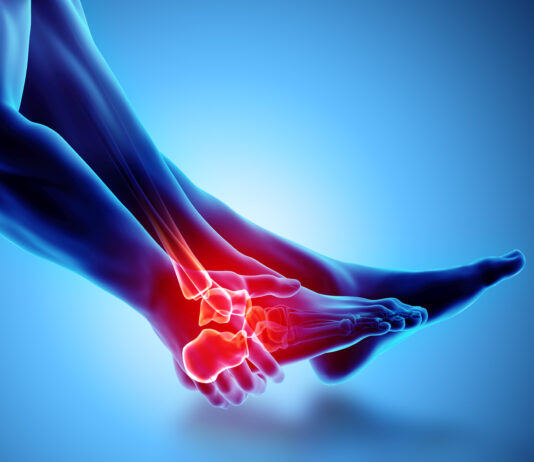

Frattura di caviglia: benefici della crioterapia di terza generazione preoperatoria

Abbastanza frequente tanto tra gli anziani, quanto tra i giovani, le fratture di caviglia vengono spesso trattate con...